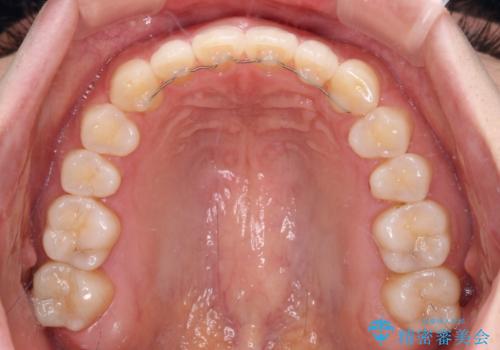

すきっ歯とオープンバイト インビザライン・ライトで改善

- 9ヶ月

すきっ歯程度の軽度の歯列不正であったため、インビザライン・ライトにより咬合改善を行うこととしました。

オープンバイトやすきっ歯は、舌突出癖によりあっという間に後戻りをするため、矯正治療前からトレーニングを行っていただき、更には後戻り防止のワイヤーリテーナーを併用しています。